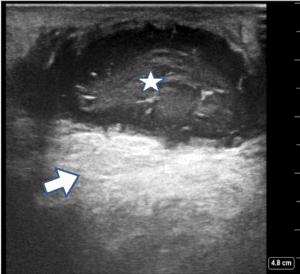

An agitated saline contrast POCUS was then performed. Cardiac POCUS during injection of saline bubbles from the left cubital vein showed bubbles entering the coronary sinus and then the right atrium (RA; online Video S2). When injection of the saline bubble was performed from the right cubital vein, the agitated saline contrast enhanced the RA before the coronary sinus, suggesting PLSVC with normal right superior vena cava (SVC). Transesophageal echocardiography showed an atrial septal defect of the superior sinus venosus type with left-to-right flow (Figure 2). The RA and the RV were dilated. She had moderate tricuspid regurgitation with an estimated pulmonary artery pressure of 40 mmHg. After agitation with saline, the bubbles failed to cross the left atrium (LA) through that presumed defect. The left and right lower pulmonary veins could be seen, but the upper ones could not. The RV and LV ejection fractions were preserved.

Figure 2. Transesophageal echocardiography showed an atrial septal defect of the superior sinus venosus type with Left to Right flow. RA, right atrium; LA left atrium; S atrium septum with septum defect.